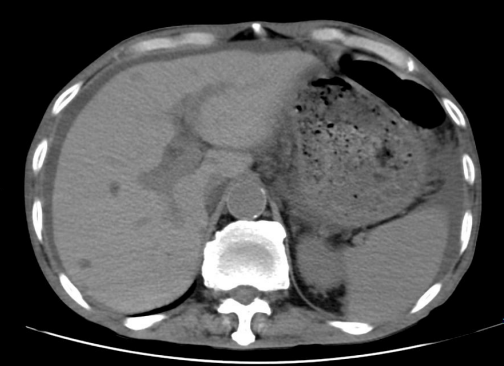

患者,男,70岁,因“双下肢麻木2年”,感觉异常,右下肢肌力4级,需搀扶,于2025年3月至外院神经内科就诊。肌电图检查示双下肢感觉运动神经受损,呈脱髓鞘改变。且发现血IgA L升高,SPE阳性,血清VEGF 295 pg/mL(升高)。腹部超声示肝硬化、脾大、腹水、双下肢水肿,肾功能示肌酐138 μmol/L。2025年4月转至外院血液内科,骨髓检查无明显异常。PET/CT示脊柱多发椎体及骨盆多发硬化改变,部分糖代谢增高(T12为著)。

图1.  PET/CT检查结果

本例患者符合以下诊断标准:主要标准包括周围神经病变(双下肢麻木、感觉异常、肌力下降,肌电图示感觉运动神经受损)、克隆性浆细胞增殖性疾病(IgA λ型M蛋白阳性,T12椎体病理示异常浆细胞20%,Lambda限制性表达)、硬化性骨病变(PET/CT示脊柱多发椎体及骨盆多发硬化改变)、VEGF升高(295 pg/mL);次要标准包括脾大(脾厚5.2 cm)、水负荷增多(腹水、双下肢水肿)、内分泌病变(甲状腺功能减退)。因此,该患者POEMS综合征诊断明确。

本例病例为临床POEMS综合征的诊疗提供了重要启示:其一,POEMS综合征临床表现复杂多样,早期识别是关键。本例患者以双下肢麻木为首发症状,首诊于神经内科,辗转多个科室方明确诊断,提示对于慢性进展性周围神经病变,尤其是合并M蛋白阳性或骨病变者,应尽早完善VEGF检测及全身影像学评估,避免漏诊误诊。其二,硬化性骨病变是POEMS综合征的重要特征。与多发性骨髓瘤的溶骨性病变不同,POEMS综合征以硬化性骨病变为主,PET/CT对发现此类病变具有重要价值,必要时需行穿刺活检以明确克隆性浆细胞浸润。其三,多学科协作(MDT)是POEMS综合征诊疗的重要保障,神经内科、消化内科、血液科、骨科等科室的联动配合,能够实现对多系统症状的全面评估,助力精准诊断与治疗方案的制定。